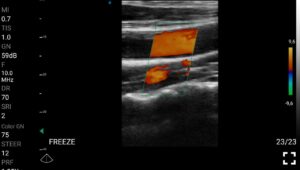

Παραδείγματα

Ολες οι παραπάνω απεικονιστικές εξετάσεις έχουν ληφθεί από φορητή συσκευή όπως: Apple Iphone, Tablet, Samsung Mobile Phones και διάφορες άλλες φορητές συσκευές.

Παραδείγματα Video